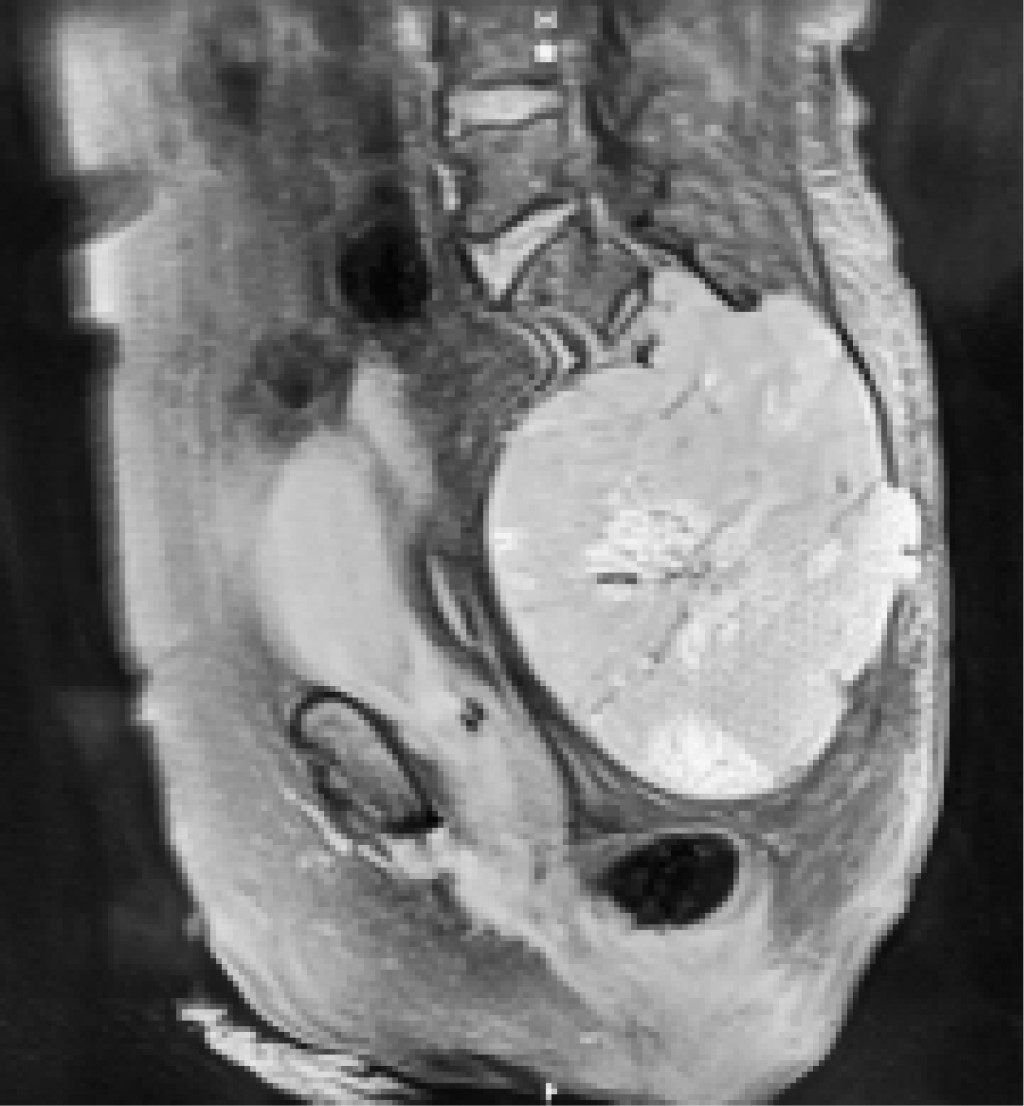

Figura 1

Figura 2

Figura 3

Figura 4

Figura 5

Figura 6